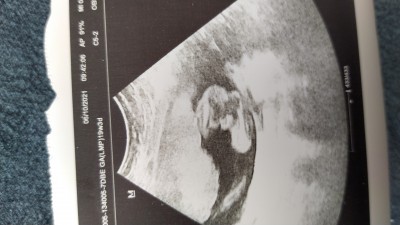

Doktor erkek dedi hatta bana bu fotoğrafını verdi de bana ya hala kızmış gibi geliyor erkek anneleri bu erkek pipisi mi ilk bebek olunca insan böyle işte şüpheleniyor her şeyden:angel:

image

Evet canm doktor bacak arasinin ultrason resmini vermis orda minik bi cikinti var o pipi :D ben de kizim olmasini cok istedigimden doktoru baya darladim yanlis gormussunuzdur diye o da bana bacak arasini vermisti ayni boyle suan 7 aylik oglum var :))

Kuzum tabi doktordan iyi bilemeyiz ama resimdeki pipiyi  göremiyorum ben acaba kız olabilir mi, senin için kendi usg fotomu paylaşıyorum burda benimkinin net belli oluyor 16 haftalık

Açıkçası bana da öyle geldi pipiye benzemiyor gibi geldi :(